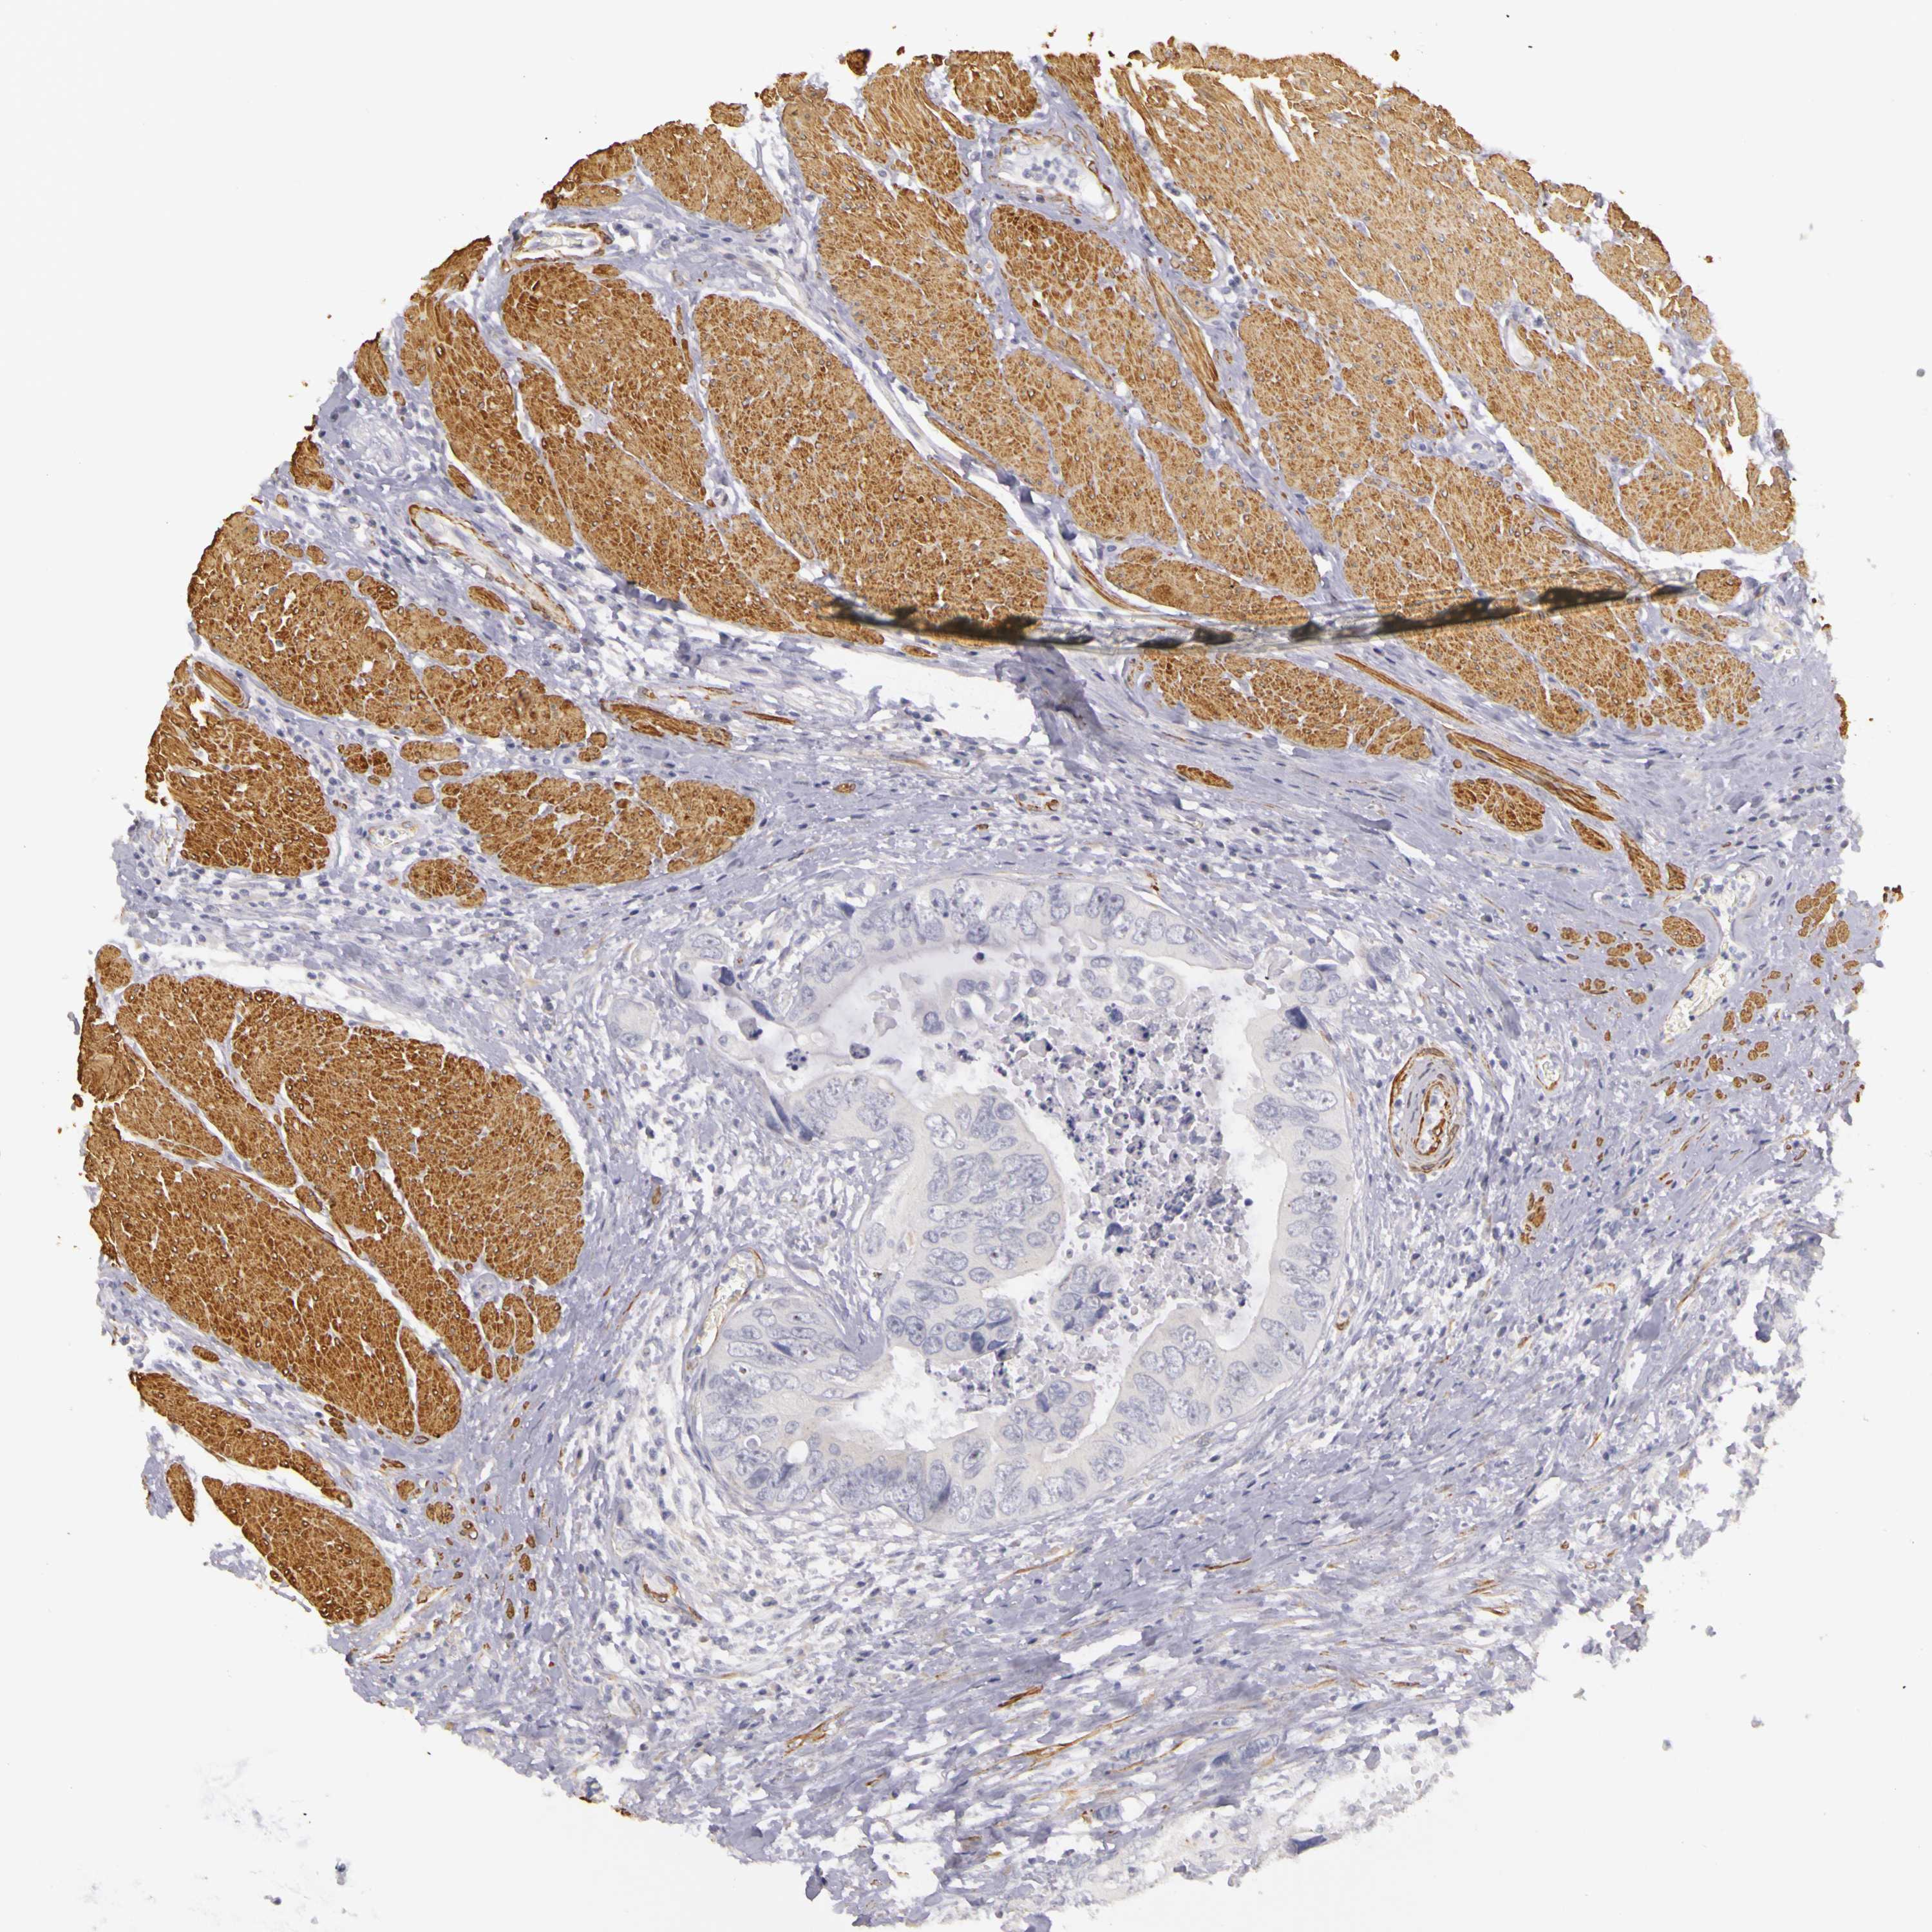

CANCER COLORECTAL CANCER Show tissue menu

Colorectal cancer

Human cancer

Colon adenocarcinoma